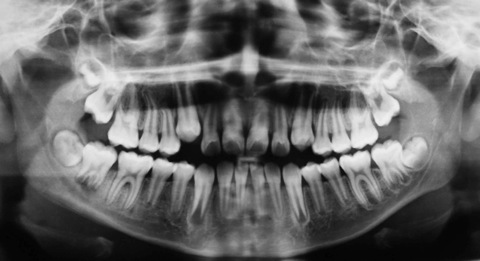

RADIOGRAFÍAS

RADIOGRAFIA

Su dentista puede prescribirle una radiografía panorámica (ortopantomografía), que proporcione una visión completa del maxilar superior, inferior y de la articulación. También le puede indicar la realización de radiografías intrabucales. La radiografía es un método que nos ayuda en el diagnóstico de: dientes retenidos, abcesos, quistes, tumores, puntos de caries, situación de las muelas del juicio, localización de estructuras anatómicas, problemas de la articulación. La paciente embarazada, o que crea que pudiera estarlo, debe advertirlo a su dentista, pues está totalmente contraindicado realizar radiografías en gestantes.